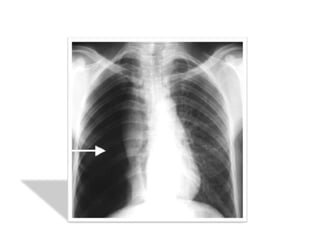

Résultats :

• hyperclarté avasculaire homogène périphérique

prenant tout l’hémithorax plus ou moins étendue.

• Rétraction du poumon s/f d’un moignon hyperdense

sur le hile avec distension des EIC et une netteté

anormale des côtes.

• La plèvre viscérale qui entoure ce moignon apparaît

sous forme d’un fin liséré opaque net comme tracé au

crayon

on recherchera systématiquement les signes

radiologiques associés :

• Une opacité liquidienne à niveau horizontal de la base

témoignant d’un hydropneumothorax

• Position du médiastin et du cœur éventuellement

refoulé

• Anomalies parenchymateuses homo ou contolatérales

en sachant qu’il existe une surcharge vasculaire réflexe

du coté sain

• Un aspect de petit cœur dans les formes bilatérales

• Décollement partiel avec angle de

raccordement aigu à la paroi ou présence de

brides sous forme de bande opaque

• On a une hyperclarté homogène périphérique

en croissant dépourvue de trame pulmonaire

• Si l’épanchement gazeux est minime on peut

avoir une fine bande claire et un « trapping »

cad une zone d’air du décollement qui ne se

vide pas à l’expiration forcée

• Bride rattachant le poumon à la paroi(risque

de rupture et d’hémothorax)